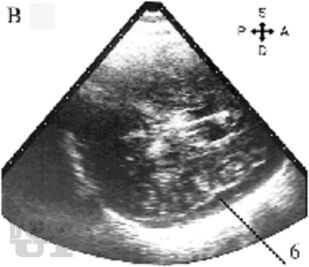

Учебное пособие содержит материал по анатомо-физиологическим особенностям новорожденных, биомеханике родовых повреждений головы и клинической картине родовых травм. Приведены инструментальные методы оценки функционального состояния головного мозга и принципы консервативного и хирургического лечения детей с родовой травмой, а также клинические примеры, тестовые задания и ситуационные задачи.